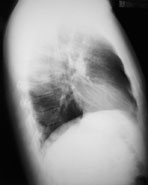

Radiologie Quiz 34

Ein 41-jähriger Mann sucht Sie auf, weil er zum dritten Mal in diesem Winter erkältet ist und dieses Mal sogar mit Fieber. Er gibt ausserdem an, etwas trockenen Husten zu haben. Ausserdem besteht seit Wochen eine Sinusitis, die nicht so recht abheilen will.

Gewichtsverlust wird verneint. Der Patient ist Nichtraucher und fühlte sich bis anhin gesund.

Die Lungenperkussion und -auskultation ist unauffällig. Das Labor zeigt eine Leukozytose ohne Linksverschiebung und ein CRP von 97 mg/dl. Hier das Röntgenbild der Lunge:

Thorax seitlich

Welche Befunde fallen Ihnen auf?

Es ist klar, dass aufgrund dieses Befundes keine Diagnose gestellt werden kann. Welche Diagnose ist aufgrund der Klink und des radiologischen Befundes am wahrscheinlichsten?